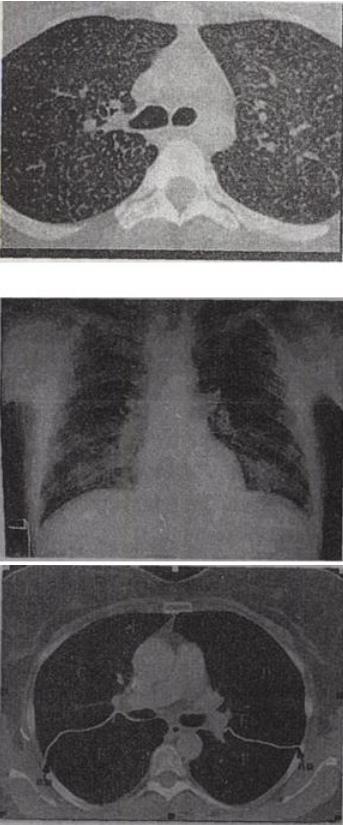

患者男,36岁,低热、咳嗽、咳痰,体重减轻,结合CT图像,最可能的诊断是()。

A、病毒性肺炎

B、粟粒型肺结核

C、矽肺

D、肺转移癌

E、细支气管肺泡癌

B